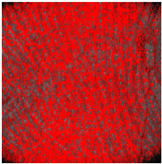

Thus, D-OCT provides images of the superficial vascular plexus. In healthy skin, en-face views show a fine vascular network with decreasing vessel size at each point of arborization (Figure 4a).

Figure 4.

Dynamic OCT image visualizing vascular network (all en-face views). (a) Healthy skin with intact vascular plexus, (b) superficial burn with partially disrupted vascular network, (c) deep burn that is totally disrupted, truncated vessels, and (d) deep burn with absent vascular plexus.

Burn injuries may damage the vascular architecture, and the reticular structure may disappear partially (1 point; Figure 4b) or completely (2 points; Figure 4c, d). First, small vessels disappear (Figure 4b), leaving only relatively thick vessels without branches (Figure 4c).

The preservation of the vascular pattern in our patients, as visualized in Figure 4b, was associated with spontaneous wound healing.